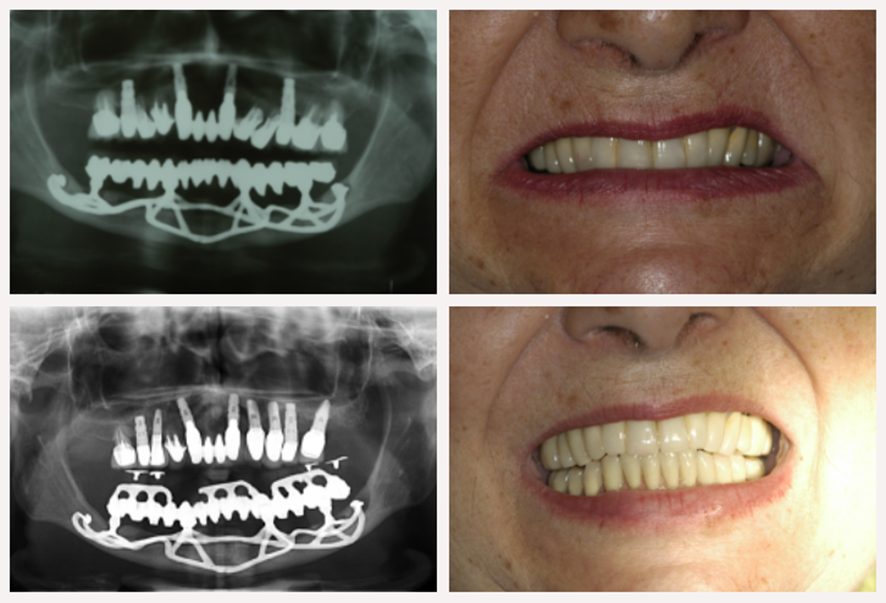

Para entendermos a resposta muito interessante que o Niltão me deu, vale a pena relembrarmos como funcionavam estes implantes. Na verdade, os implantes subperiósteos, também chamados de justaósseos, eram implantes de superfície. Ou seja, não penetravam na intimidade do tecido ósseo, mantendo uma relação de contato com o osso por justaposição. Preliminarmente, eles foram desenvolvidos pelo sueco Gustav Dahl, em 1943, e contavam com uma estrutura metálica de cromo-cobalto-molibdênio que era fabricada sobre um modelo de gesso previamente obtido do osso exposto do paciente durante a cirurgia. As Figuras 1 e 2 ilustram este tipo de implante.

Niltão recorda que o Dr. Sérgio Jayme mostra sempre um caso de justaósseo inferior feito pelo Niltão na década de 1970. Ele trocou a prótese apenas porque estava muito desgastada, mas os implantes estavam lá, bem firmes, e o justaósseo estava perfeito. O Dr. Sérgio Jayme continua dando manutenção neste caso, que agora já está com mais de 40 anos de acompanhamento.

Eu mesmo me lembro bem deste dia que o Dr. Sérgio Jayme apresentou este caso. Foi no primeiro Meeting Internacional da Implacil De Bortoli, em 2012, e eu estava sentado ao lado do Dr. Nilton De Bortoli quando o Dr. Sérgio Jayme fez sua apresentação e homenageou o Niltão. Ao fim da apresentação, foram mostradas imagens da paciente com os implantes em perfeitas condições e com uma prótese nova sobre os implantes antigos. Tratava-se de uma prótese com dentes maiores (houve a necessidade de aumento da dimensão vertical), pois a antiga havia se desgastado com o tempo. Niltão olhou tudo aquilo e cochichou no meu ouvido: “Ficam aumentando muito o tamanho desses dentes e essa dimensão vertical da paciente, e daqui a pouco vão perder os meus implantes”.